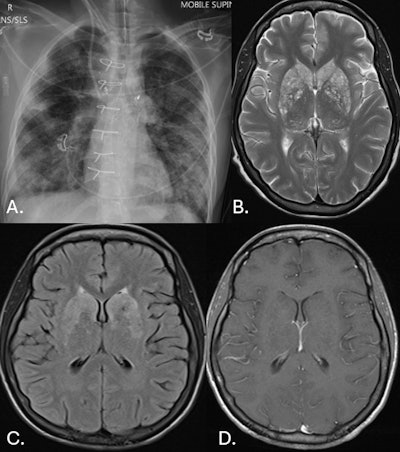

26-year-old woman. (A.) CXR frontal: bilateral, patchy consolidation consistent with pneumonia. (B.) MR brain axial T2: extensive, small hyperintense lesions involving the basal ganglia. This is consistent with engorged and dilated perivascular spaces, which is consistent with pseudocyst formation. (C.) MR brain axial FLAIR: extensive, small hyperintense lesions involving the basal ganglia. (D.) MR brain axial T1 + contrast: there is no contrast enhancement of the lesions demonstrated on T2 and FLAIR imaging.